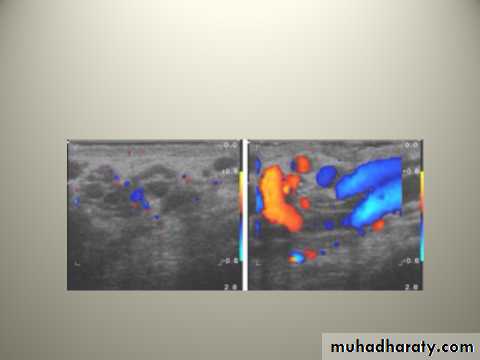

VARICOCELE

It is a varicose dilatation of the veins draining the testis ( abnormal dilatation of the pampiniform plexus)Most varicoceles present in adolescence or early adulthood

Usually on the left.

Clinical Features

Usually symptomless

There may be dragging scrotal discomfort

The scrotum on the affected side hangs lower than normal

On palpation, with the patient standing, the varicose plexus feels like a bag of worms.

Infertility ?

Investigations: Scrotal Doppler U/S